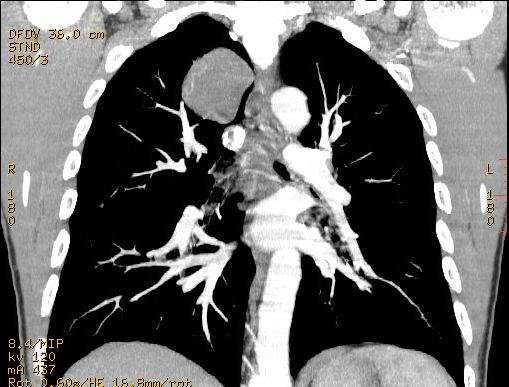

不过重建的图片上看到肿块内可见强化的血管影,不是很支持。

右肺见纵隔旁见类圆形界清等密度肿块影,直径约5.0cm,增强呈不均匀强化,重建的图片上看到肿块内可见强化的血管影,考虑:1,肺腺瘤;2,肺肉瘤。

肿块内可见强化的血管影,支气管囊肿不支持。

肺内肿块、从轴位像看具备了良性肿块的特点;而重建图像有强化、浅分叶,恶性病变亦不能出外。期待结果。